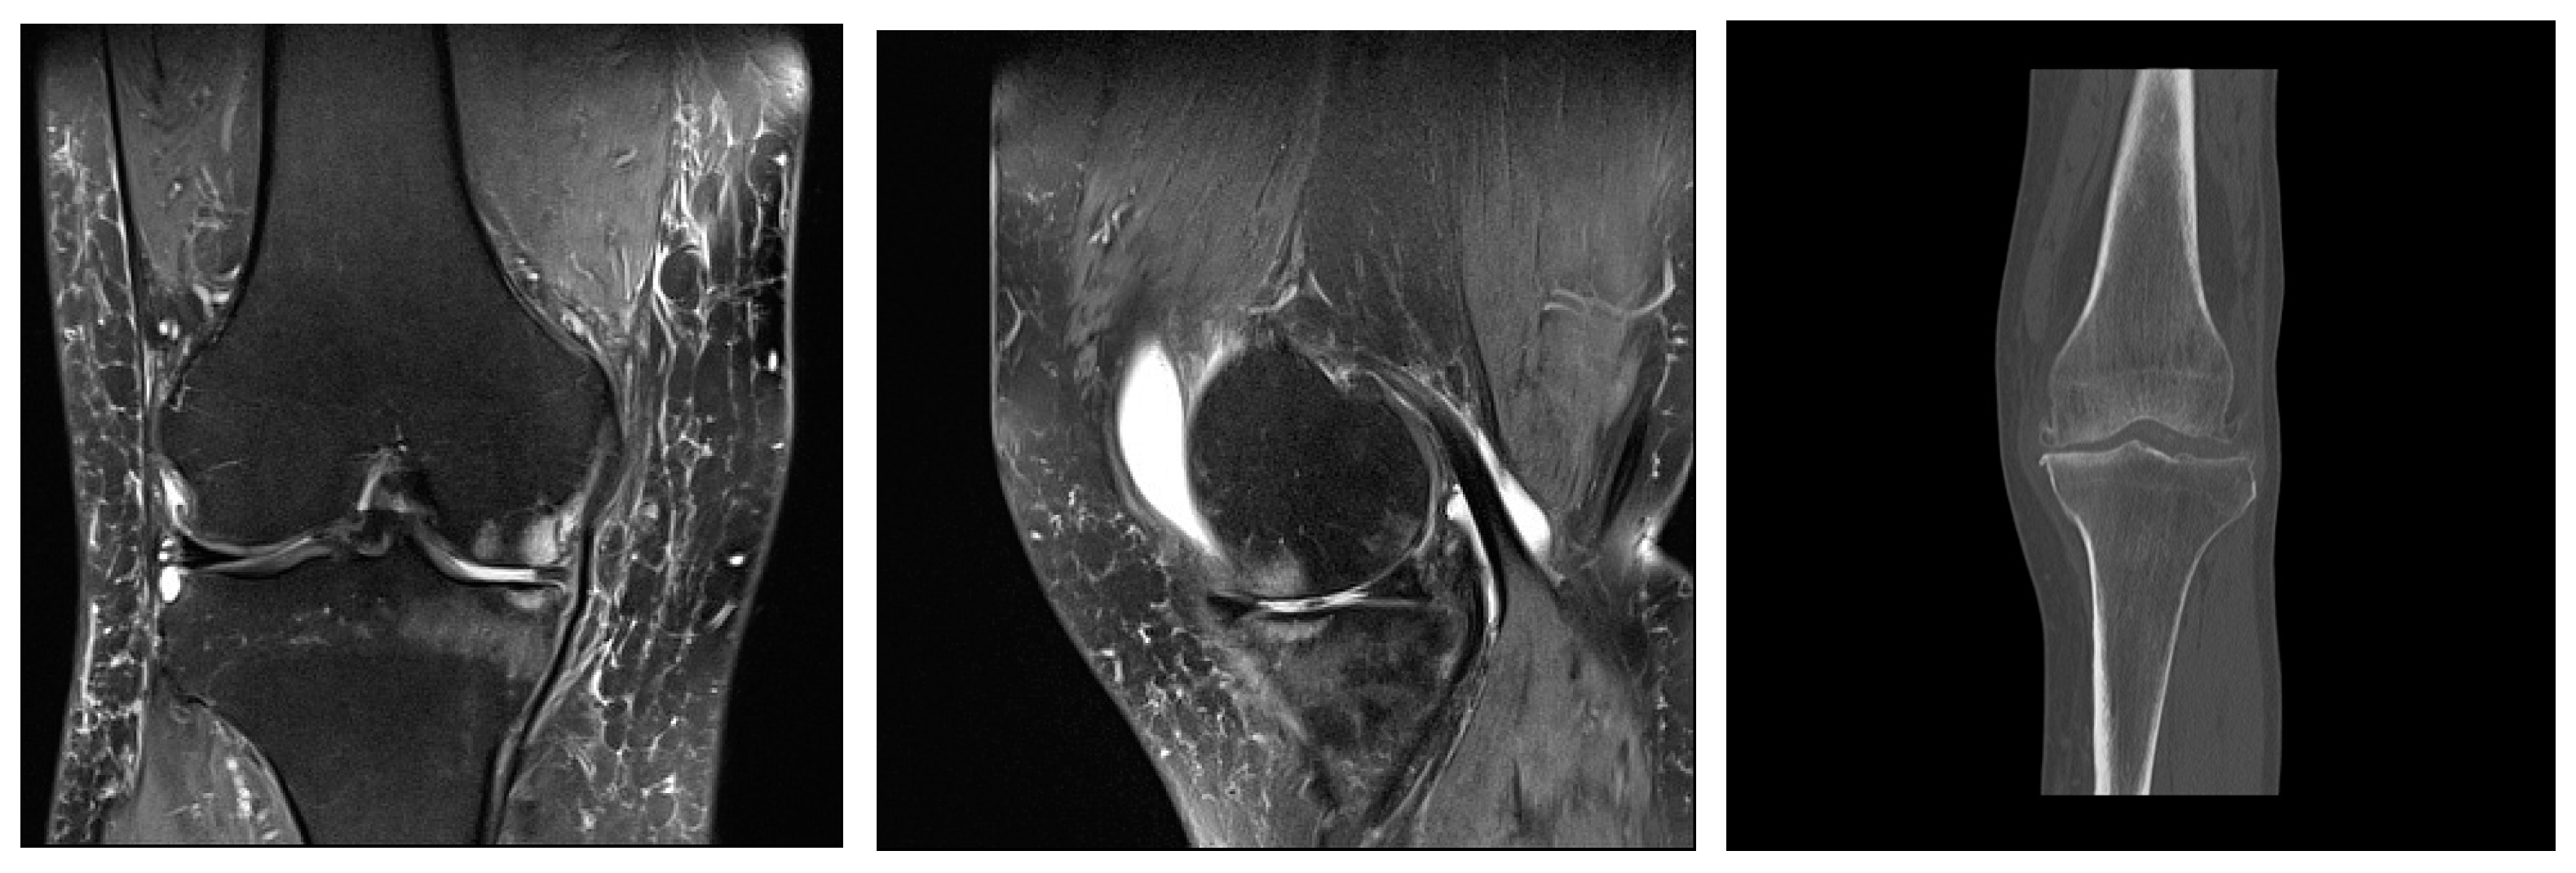

Figure 2. Mild deforming gonarthrosis visualized by MRI (proton-density fat saturated sequences in sagittal and coronal plane) and by CT (multiplanar reconstruction, coronal plane). Patchy areas of subchondral bone edema of femoral and tibial articulations with numerous marginal osteophytes. Articular cartilage is denuded in medial compartment, while in lateral compartment I-II degree hondromalacic changes are seen. Narrowed articular spaces with reactive effusion propagating to suprapatellar bursa are seen. High signal intensity of menisci and cruciate ligaments suggestive of degenerative changes. Ruptured medial meniscus. Reactive edema of periarticular and subcutaneous soft tissues.

In early osteoarthritis changes, visible on magnetic resonance imaging (MRI), there are subchondral sclerosis and cysts in the bone tissue, lesions in the surrounding bone marrow, fissures in the articular cartilage (Figure 2), and changes in the synovial membrane [55].